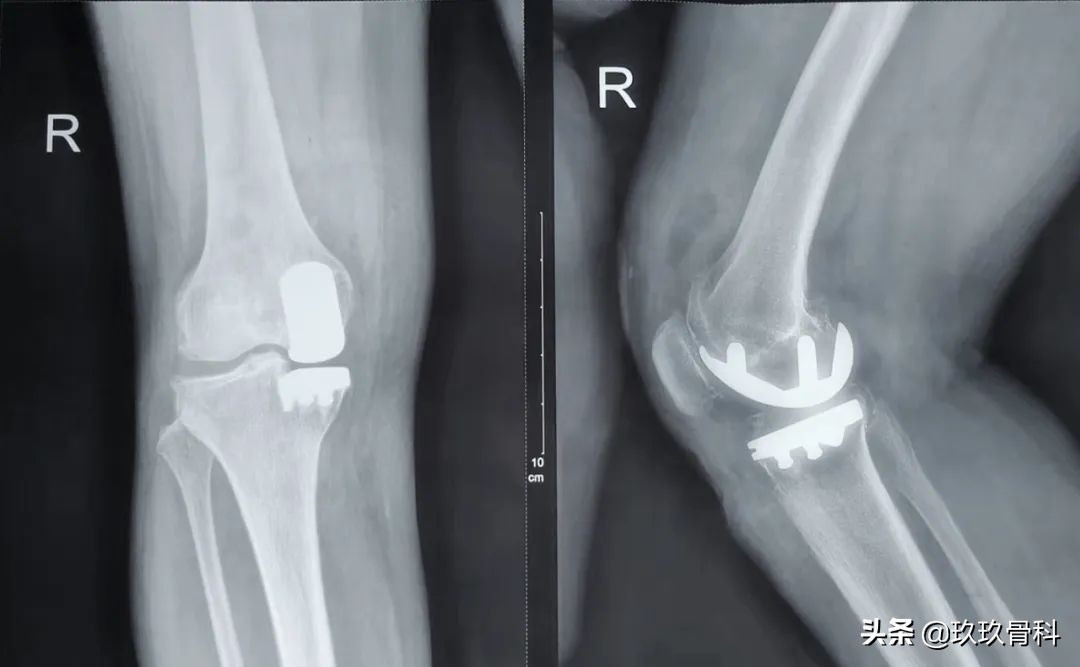

术后影像